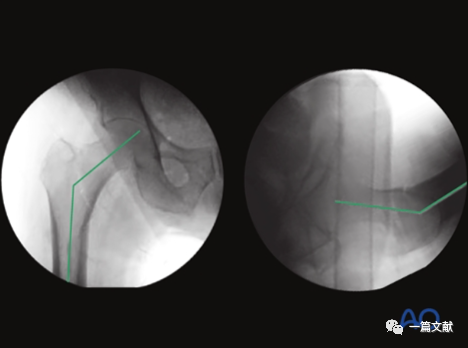

左侧正位片显示颈干角,右侧侧位片显示前倾角。

从侧位片基础上抬C臂机约15°即轴位片,如下:

下图左侧正位片与右侧的轴位片,显示了内固定的良好位置(位于头颈中心与髓腔中心)。需要注意的是这些标准的术中透视图像,只有在良好骨折复位的基础上才能获得。

只有如下图右侧的轴位片图像才能判断内固定在头颈骨块中的位置(左侧为侧位片)